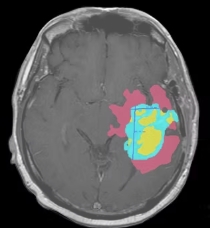

PyTorch • 3D U-Net • MRI • 2025

Multi-class segmentation of edema, non-enhancing, and enhancing tumors using custom Soft Dice Loss.